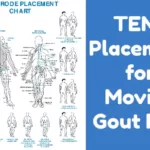

Now that technology allows us to see tophi growing into cartilage, tendons, and bones, we can see it is not wise. I’ve added some more important 2014 information to this 2010 article about early detection of joint damage from new gout scanning technology. First let us see how this technology shows early tophi leading to bone erosion and severe, painful, joint damage.

It has been a few years since improvements in scanning techniques allowed us to view what is happening inside joints. Over 3 years ago, I quoted from Dalbeth [1]:

There is a strong relationship between bone erosion and the presence of intraosseous tophus. These results strongly implicate tophus infiltration into bone as the dominant mechanism for development of bone erosion and joint damage in gout.

A significant part of Dalbeth’s, and related research, is the observation that DECT reveals urate deposits much more effectively than any other technique, to the point that joints often show uric acid deposits prior to any physical or inflammatory indication of gout.